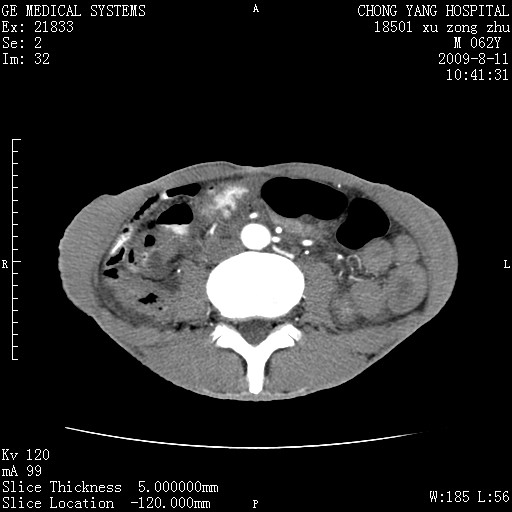

以下是引用杀毒软件在2009-8-11 16:35:00的发言:[br]肝内胆管扩张局限于左叶,胆管内有结石伴肝外胆管结石,胆管壁增厚呈弥漫性并发腹腔积液,胰腺边界模糊。[br][br]考虑---胆总管及肝内胆管结石继发胆管炎及胰腺炎,左肾下极囊肿,腹水。

以下是引用zjzjr在2009-8-11 17:35:00的发言:[br]肝内胆管扩张局限于左叶,胆管内有结石伴肝外胆管结石,胆管壁增厚呈弥漫性并发腹腔积液。[br][br]考虑---胆总管及肝内胆管结石继发胆管炎,左肾下极囊肿,腹水。